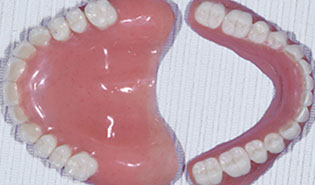

v) Fabricating temporary and permanent restorations

vi) Placing temporary and permanent restorations for a beautiful new smile